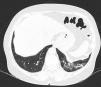

El USP se realiza a través de los espacios intercostales con la sonda perpendicular a la superficie torácica en posición longitudinal, apoyando sus extremos proximal y caudal sobre las costillas superior e inferior que delimitan el espacio intercostal. Las referencias óseas son las crestas óseas costales. La pleura visceral y parietal se representan como una sola línea ubicada 0,5cm por debajo de las crestas costales, llamada «línea pleural». La apariencia de las 2 imágenes costales con la línea pleural intermedia se conoce como el «signo del murciélago» (fig. 1).

Imagen de ultrasonido normal realizado en paciente sano, obtenida con equipo GE Logiq 3 con transductor lineal multifrecuencia de 10-14MHz, en el tercer espacio intercostal derecho, con paciente en posición decúbito supino y transductor en orientación longitudinal. A) Imagen original. B) Resaltado en amarillo piel y tejido celular subcutáneo; en rojo, capas miofasciales; en verde, costillas y la sombra acústica qgenran; en morado, línea pleural, y en azul, líneas A.

En el pulmón normal, debido a la gran diferencia de impedancia acústica entre el aire y los tejidos blandos circundantes, la pleura se comporta como reflector casi perfecto de las ondas de ultrasonido; produce múltiples fenómenos de reverberación entre la línea pleural y la sonda. La línea pleural se visualiza hiperecoica, brillante, delgada y regular, con movimiento deslizante suave y sincrónico con la respiración llamado «deslizamiento pulmonar». Debajo de la línea pleural hay artefactos horizontales característicos: «líneas A», que son réplicas de la línea pleural dispuestas de forma equidistante entre sí debido a la reverberación del ultrasonido en la línea pleural y artefactos resultantes de las capas miofasciales de la pared torácica debido a fenómenos de reverberación menores y efectos de espejo24.